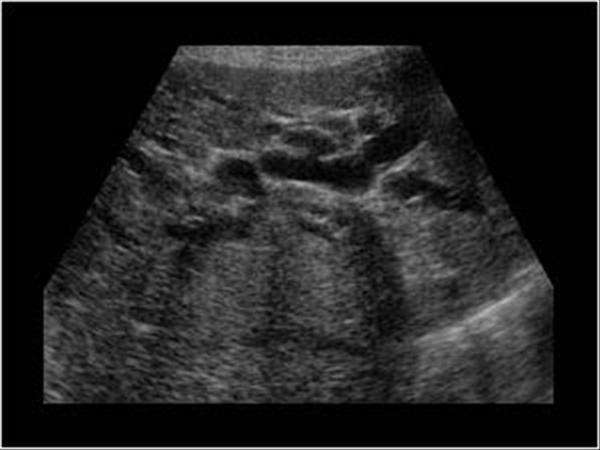

What is Polycystic liver disease?

This is an autosomal dominant genetic disease in which multiple small cysts cover the liver. 60% of patients with polycystic liver disease will have polycystic kidney disease.

What is the sonographic appearance of Polycystic liver disease?

Anechoic

Thin well-defined walls

Posterior

enhancement

Multiple

Varying in small size